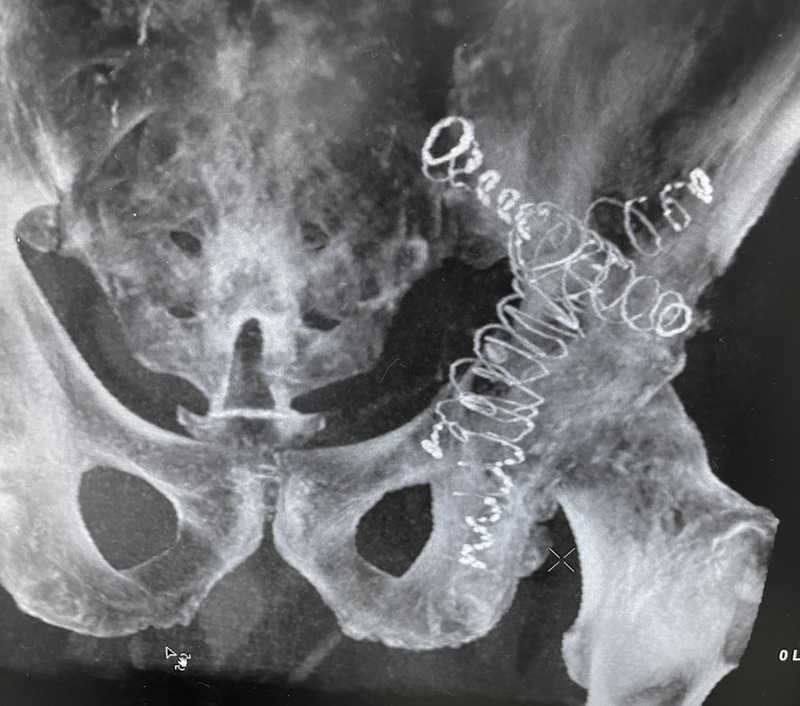

The 63-year-old patient presented with a pathologic acetabulum/hemi-pelvic fracture, and osteolysis with uncontained defect from metastatic lung cancer and additional co-morbidities. The patient has been treated with radiation for metastatic bone disease of the pelvis, and was bed ridden living in a skilled nursing facility due to severe pain and dysfunction resulting from his pathologic pelvis fractures. The patient was brought to surgery and IlluminOss implants were inserted percutaneously through the posterior column, anterior column and LC2 to provide fill and stability for the uncontained osteolytic defect. The implants were filled with a photodynamic liquid monomer and cured with visible blue light. At post-op day 1, the patient was weight bearing as tolerated using a walker. The patient was discharged back to the SNF on post operative day 1 and then from the SNF to home at 2 weeks post procedure. At 6 weeks follow up, patient uses the walker in the community and ambulates unassisted intermittently at home.